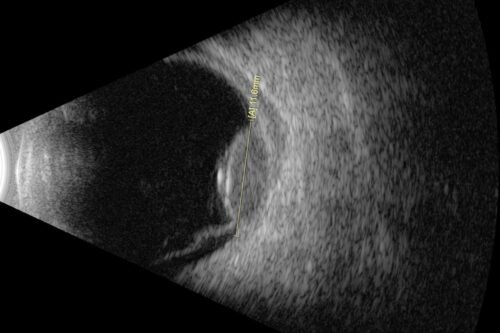

Every angle covered

In anterior wide-field mode, Eye One™ allows you to view the entire segment to identify causes of glaucoma-related disease, and to accurately and consistently measure key angle parameters.